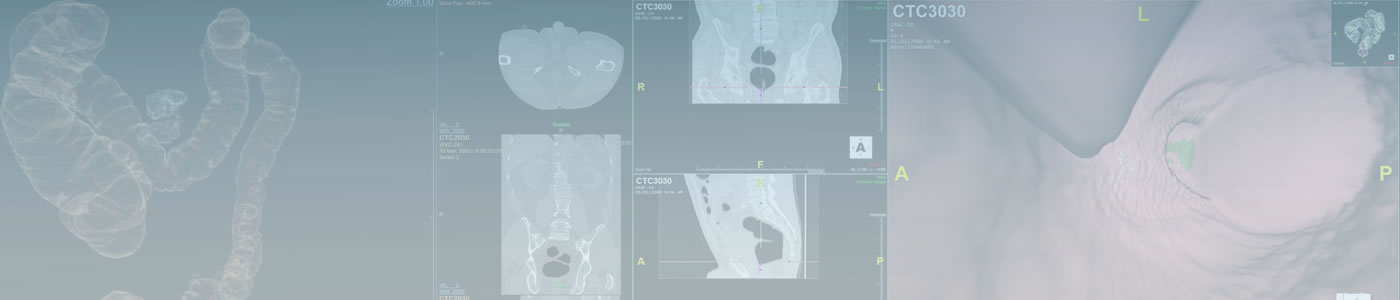

CT Colonography

CT Colonography (CTC) is an evolving technique with considerable potential for widespread screening of colorectal cancer. Application of appropriate techniques and knowledge of correct interpretation skills are vital to successfully implementing this technique.